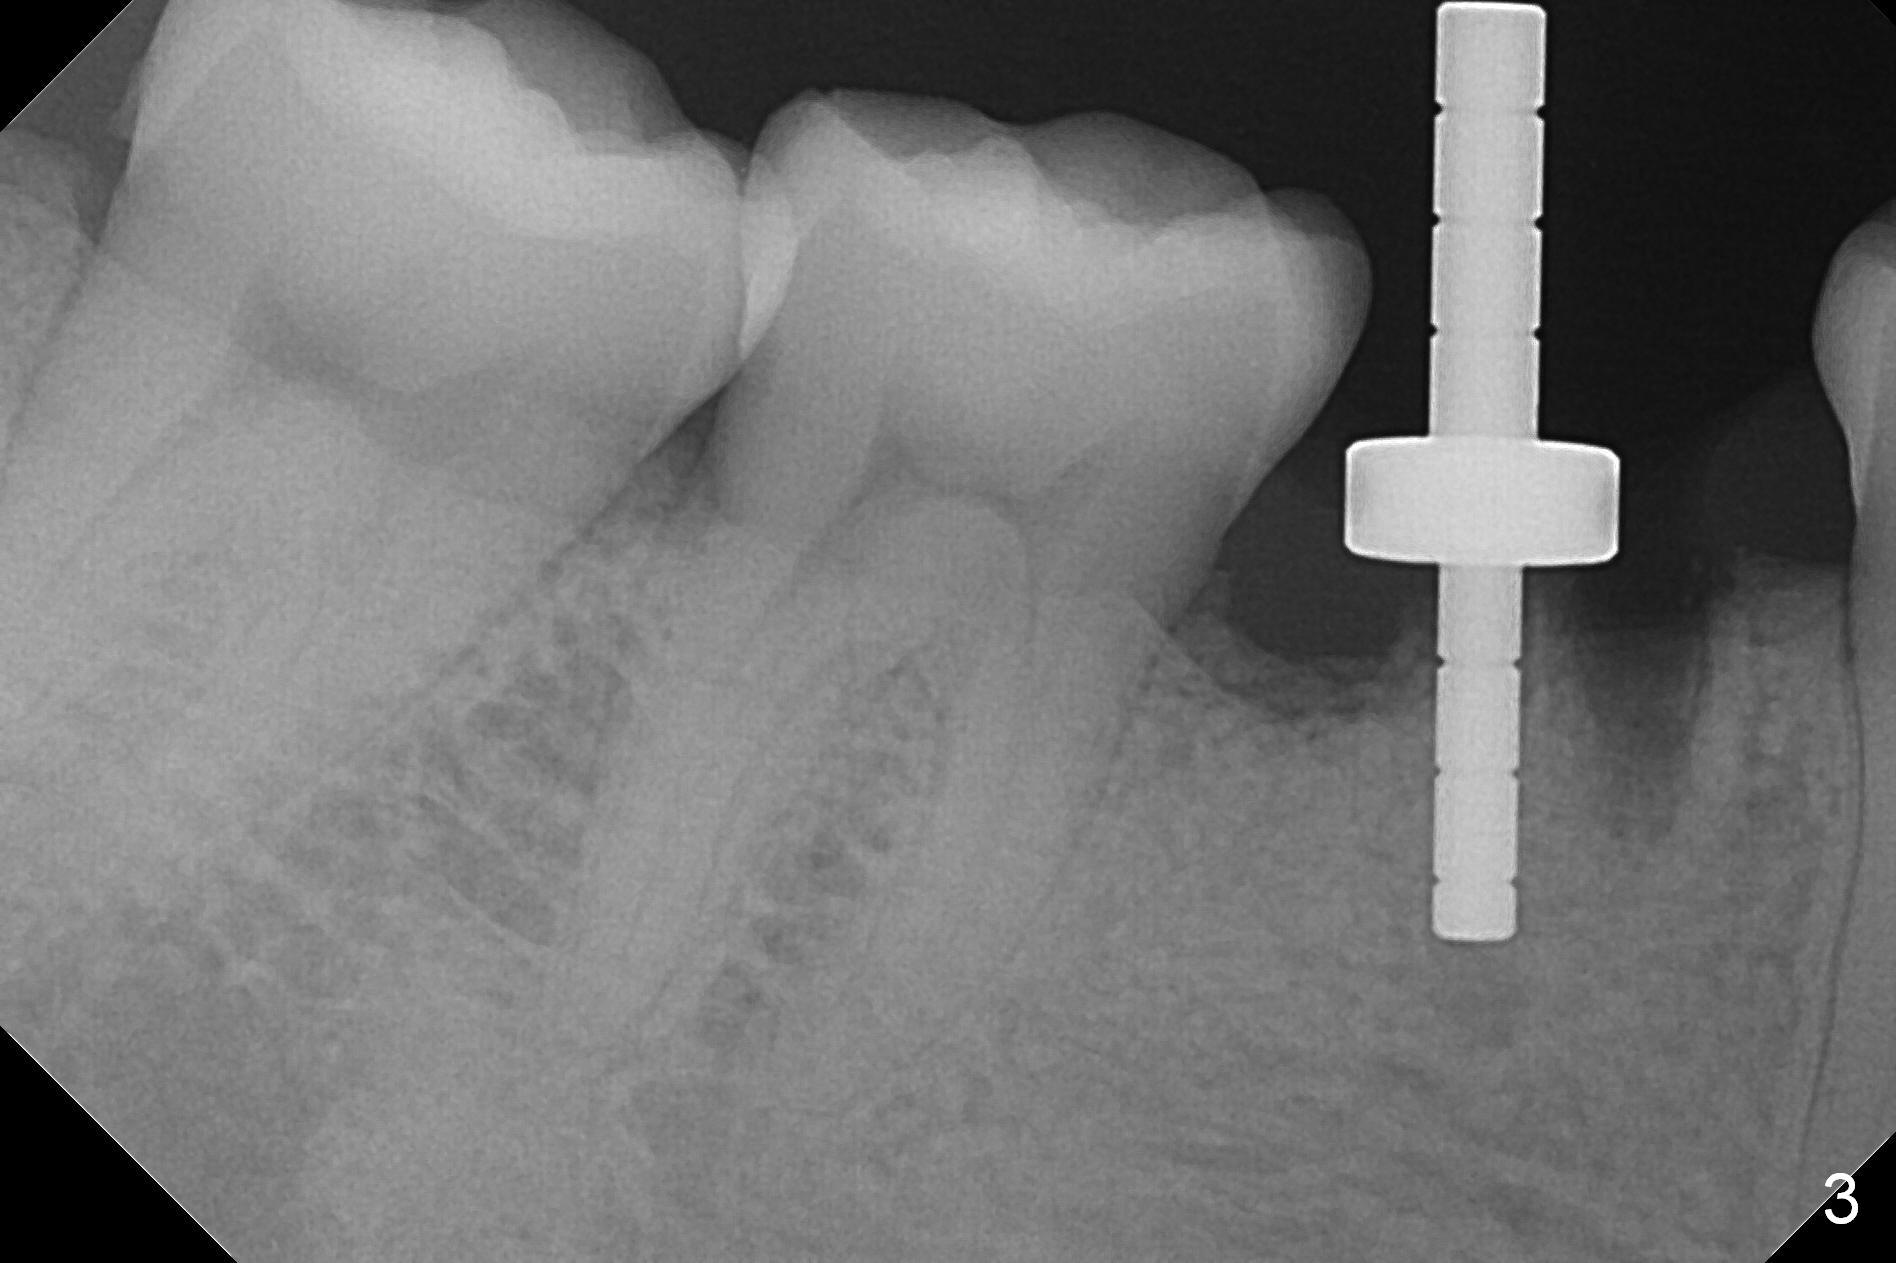

The lower 2nd primary molar has buccal furca lesion (Fig.1 *) with the thin buccal plate (Fig.2). Osteotomy is initiated in the sloped septum (Fig.3). After use of Magic Drill (MD) 3.3 mm for 13 mm and MD 3.8 mm for 11 mm, placement of a 4x11 mm IBS implant meets resistance because of the dense bone (Fig.4-6, red dashed line: Mental Loop) with final insertion torque >50 Ncm. After placement of a 6x4(3) mm abutment and autogenous bone in the remaining shallow sockets (Fig.6), a provisional is fabricated (Fig.7). Finally periodontal dressing is applied. Impression is taken 3 months postop (Fig.8). Buccal infection develops 2 weeks post cementation (Fig.9). When the crown/abutment is removed, there is no residual cement. The implant threads can be felt through the fistula. After soft tissue debridement and copious irrigation, Arestin is placed in the fistula. The latter disappears 15 days post debridement. The patient feels better and moves out of state. It appears that early periimplantitis develops because of the preexisting buccal furca lesion and failure to place the implant deep. The implant will be placed deep after loosening a little (since there is apical space (Fig.8 white line)) or removed, truncated at the apex and placed lower than the buccal crest.